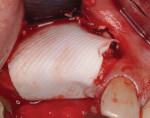

After 10 weeks of healing, the patient returned for surgical uncovery of the two implants and connection of healing abutments (Figure 7). Following a full-thickness flap reflection to confirm osseous regeneration, the remaining collagen membrane was found relatively intact (Figure 8). It was easily removed, revealing complete resolution of the peri-implant defect and a herringbone appearance of the underlying regenerate, resembling the texture of the barrier membrane (Figure 9). The hard, nonpenetrable nature of this specific pattern, along with the white, calcified surface of the tissue, suggested that the membrane may have served as a substrate for ossification, implying the ossification of the inner aspect of the barrier, as demonstrated by Zubery et al.12

Both sites were augmented with the same mineralized bone allograft (OraGraft® FDBA) as used in the first case. Likewise, the same ribose cross-linked collagen membrane as used in the first case (Ossix® Plus) was passively adapted over the surgical site and beneath the periosteum of the buccal and palatal flaps (Figure 12). The flaps were reapproximated without achieving 100% primary closure (Figure 13).